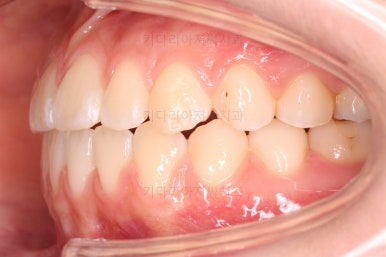

각각 왼쪽, 오른쪽의 교합의 모습입니다.

가장 좋은 교합은 위아래 치아들이 지그재그로 톱니바퀴 물리듯이 맞아들어가야 하는데 오른쪽 사진들 보면 중간중간 빈틈도 많이 보여요.

이런 교합은 장기적으로 치아 수명을 단축시킬 수 있습니다.

보시다시피 왼쪽 치열들의 교합이 뭔가 틈새가 많고 정확하지 않기 때문에 해당 부분에 미니스크류를 해서 교합을 맞춰주기로 했답니다.

아직 위아래 중앙선도 어긋나 있고, 교합도 아직은 미흡하네요.